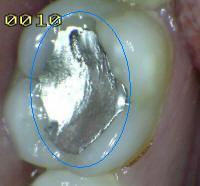

1. Restauración con amalgama

1. 5

2. SOMBRA SUBYACENTE DE DENTINA (SIN PERDIDA DE INTEGRIDAD ESTRUCTURAL)

1. HALLAZGO: sombra que trasluce una restauración

1. CRITERIO DE DIAGNOSTICO: área oscurecida, sombra intrínseca, que puede aparecer gris, azúl o café

1. ICDAS 4

2. DIAGNOSTICO

1. lesión cariosa no cvitacional

2. TRATAMIENTO

1. Operatorio

2. ACTIVIDAD

1. (Activa / inactiva